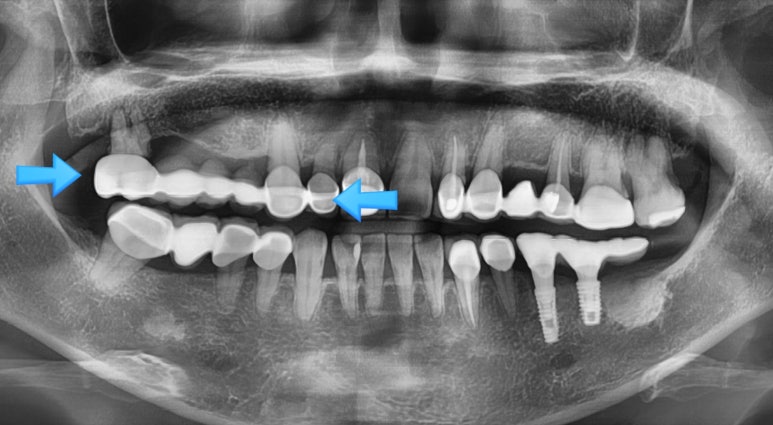

이미 임플란트 상담을 위해 다른 여러군데의 치과에서 상담을 하시고 온 환자분이었습니다.

오래 전에 다른 치과에서 한 브릿지에는 치아 뿌리 3개에 다소 긴 총7개의 머리가 있는 브릿지(파란색 화살표)

였는데요,

이 브릿지를 제거하고 발치 후 임플란트를 해야 한다는 진단을 이미 여러 치과에서 듣고 오셨습니다.

여러 치과에서 상담을 받았지만, 저희 치과에서 진행하기로 결정하셨습니다!